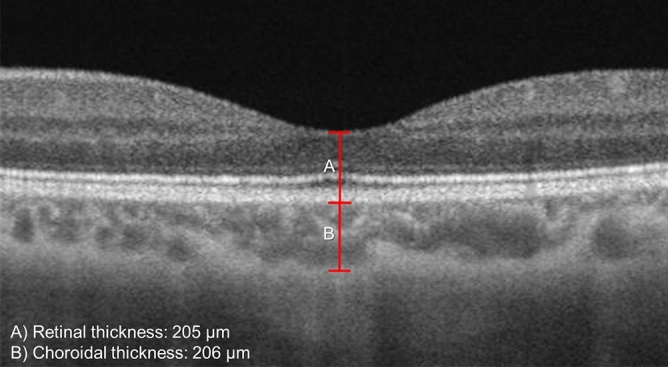

Evaluation of retinal and choroidal thickness

Two independent graders who were blinded to the scan timing, performed the measurements for retinal and subfoveal choroidal thicknesses from the 3 × 3-mm2 macula centered scan. The thicknesses were measured at the center of the fovea using MATLAB (MathWorks, MA, USA). The built-in review software (PLEX Elite Review Software, Carl Zeiss Meditec, Inc., Dublin, USA; Version 1.7.1.31492) provided the retinal thickness map. To determine the foveal pit, we scanned through several B-scans to determine the thinnest retina layer. The neighboring two B-scans were averaged for segmentation of the choroidal-scleral boundary. The retinal thickness was marked from the inner limiting membrane (ILM) perpendicular to the outer surface of the retinal pigment epithelium (RPE) whereas the choroidal thickness was marked from the outer surface of the RPE to the CSI (Fig. 3). The thicknesses were measured with the caliper function in the MATLAB presented in pixel, and subsequently converted to micrometers via an axial digital sampling of 1.95 µm/ pixel.

Figure 3.

The retinal (A) and choroidal (B) thicknesses, were manually measured at the fovea (detected as the lowest point of internal limiting membrane), using caliper measurement tool. The images were generated from the built-in review software (PLEX Elite Review Software, Carl Zeiss Meditec, Inc., Dublin, USA; Version 1.7.1.31492; https://www.zeiss.fr/content/dam/Meditec/international/ifu/documents/plex-elite/current/2660021169042_rev._a_artwork.pdf).